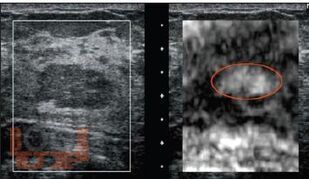

В книге освещены теоретические и клинические ключевые аспекты соноэластографического исследования, начиная от физических основ исследования и истории развития метода, до описания конкретных соноэластографических характеристик различных органов и тканей.

Учебно-методическое пособие рассчитано на ультразвуковых диагностов, гинекологов, хирургов и онкологов, специализирующихся на диагностике и лечении заболеваний молочной и щитовидной желез, органов брюшной полости и малого таза